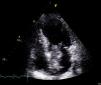

Ao exame objetivo apresentava-se hemodinamicamente estável e sem alterações relevantes. O eletrocardiograma (ECG) de 12 derivações mostrava taquicardia sinusal, com infra-ST em V4, ondas T negativas em V4-V5 e aplanadas em V6 e derivações frontais (Figura 1). Os testes laboratoriais revelaram hemoglobina 11,3g/dL, velocidade de sedimentação 84mm, proteína C reativa 6,14mg/dL, troponina I 1,89 ng/dL (com discreta subida na segunda determinação para 2,02 ng/mL) e CK-mb 8,4 ng/mL, pelo que foi internada na Unidade Coronária com o diagnóstico de EAM sem elevação do ST. O ecocardiograma transtorácico revelou compromisso moderado a grave da função sistólica do ventrículo esquerdo, com acinésia apical e hipocinésia dos segmentos mesoapicais das paredes anterior, lateral e septo interventricular. Além das alterações da contratilidade segmentar, observou-se uma volumosa massa auricular esquerda fixada ao septo interauricular, de estrutura coraliforme e aspeto friável, com cerca de 46mm de maior eixo, cuja porção mais apical prolapsava para o ventrículo esquerdo em diástole sobre o folheto anterior da válvula mitral, não condicionando obstrução fixa ao fluxo de câmara de entrada do VE (Figura 2). Dada a elevada probabilidade de se tratar de um mixoma, realizou de imediato ecocardiograma transesofágico (Figura 3), que confirmou os achados descritos em transtorácico, pelo que, mediante a possibilidade de embolização eminente, foi contactado o Serviço de Cirurgia Cardiotorácica do nosso hospital de referenciação, que aceitou receber a doente após realização de angiografia coronária, a qual mostrou artérias coronárias sem lesões angiograficamente significativas (Figura 4).

O ecocardiograma permanece como o método de eleição para o diagnóstico e a caracterização morfológica do mixoma. Foram determinados 2 padrões de mixoma por ecocardiografia: redondo, que tem aparência sólida e circular com uma superfície imóvel; e polipoide, de contornos irregulares e superfície móvel. A incidência de embolização sistémica é superior nos tumores com uma superfície irregular e friável relativamente aos de superfície lisa4, estando também associada aos tumores polipoides e que prolapsam para o ventrículo2.

No nosso caso clínico, o mixoma auricular esquerdo era polipoide com uma superfície irregular e bastante friável, que prolapsava através do orifício valvular mitral. Não obstante estas características, bem como as suas grandes dimensões, não foram documentados previamente à situação atual outros sintomas obstrutivos ou eventos embólicos periféricos.